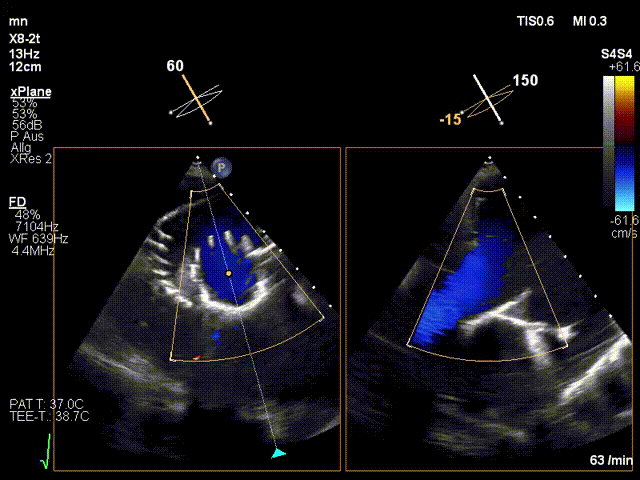

手術(shù)在全麻狀態(tài)下進(jìn)行。在加拿大圣保羅醫(yī)院的Anson Cheung教授的指導(dǎo)參與下,術(shù)者采用經(jīng)右側(cè)頸靜脈入路的方式將輸送器送入患者心臟內(nèi),在TEE及DSA引導(dǎo)下調(diào)整輸送器頭端角度,使得輸送器與三尖瓣瓣環(huán)平面垂直。在輸送器進(jìn)入右心室后釋放室間隔錨定裝置,而后釋放瓣葉夾持件(2個(gè)耳片結(jié)構(gòu))成垂直狀態(tài)。在TEE及DSA確定夾持件固定至三尖瓣葉根部且位于右室側(cè)后釋放人工瓣心房側(cè)盤片。隨后調(diào)整瓣膜同軸性以及室間隔錨定件位置(貼合室間隔),前推藏針管并固定,進(jìn)而釋放室間隔錨定裝置,并再次確認(rèn)瓣膜位置、穩(wěn)定性及同軸性,合攏輸送鞘后撤出輸送器,完成LuX-Valve Plus人工三尖瓣瓣膜的植入。

LuX-Valve Plus經(jīng)血管三尖瓣置換系統(tǒng)本次“出海”圓滿完成,術(shù)后Jörg Hausleiter教授對LuX-Valve Plus經(jīng)血管三尖瓣置換系統(tǒng)的器械性能和治療效果大為稱贊,認(rèn)為LuX-Valve Plus的手術(shù)體驗(yàn)非常好。術(shù)后即刻超聲顯示三尖瓣反流消失,血流動(dòng)力學(xué)改善顯著,患者恢復(fù)快。Anson Cheung教授也肯定了LuX-Valve Plus術(shù)中操作的便捷性,認(rèn)為LuX-Valve Plus容錯(cuò)率高,對術(shù)中影像的依賴較小,后期希望可以更多的應(yīng)用LuX-Valve Plus三尖瓣置換系統(tǒng)于臨床實(shí)踐,讓更多的三尖瓣重度反流患者盡早獲益,改善預(yù)后。